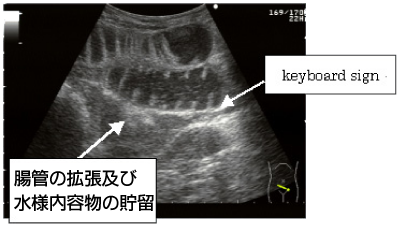

消化管病変で超音波検査の有用性が発揮されるのは、腸閉塞(画像)や虫垂炎、腹膜炎などの腹部救急疾患です。

特に、小児は腸閉塞(腸重積)を起こしやすいので、急激な嘔吐や腹痛で来院した子供には、当院では必ず超音波検査を実施します。